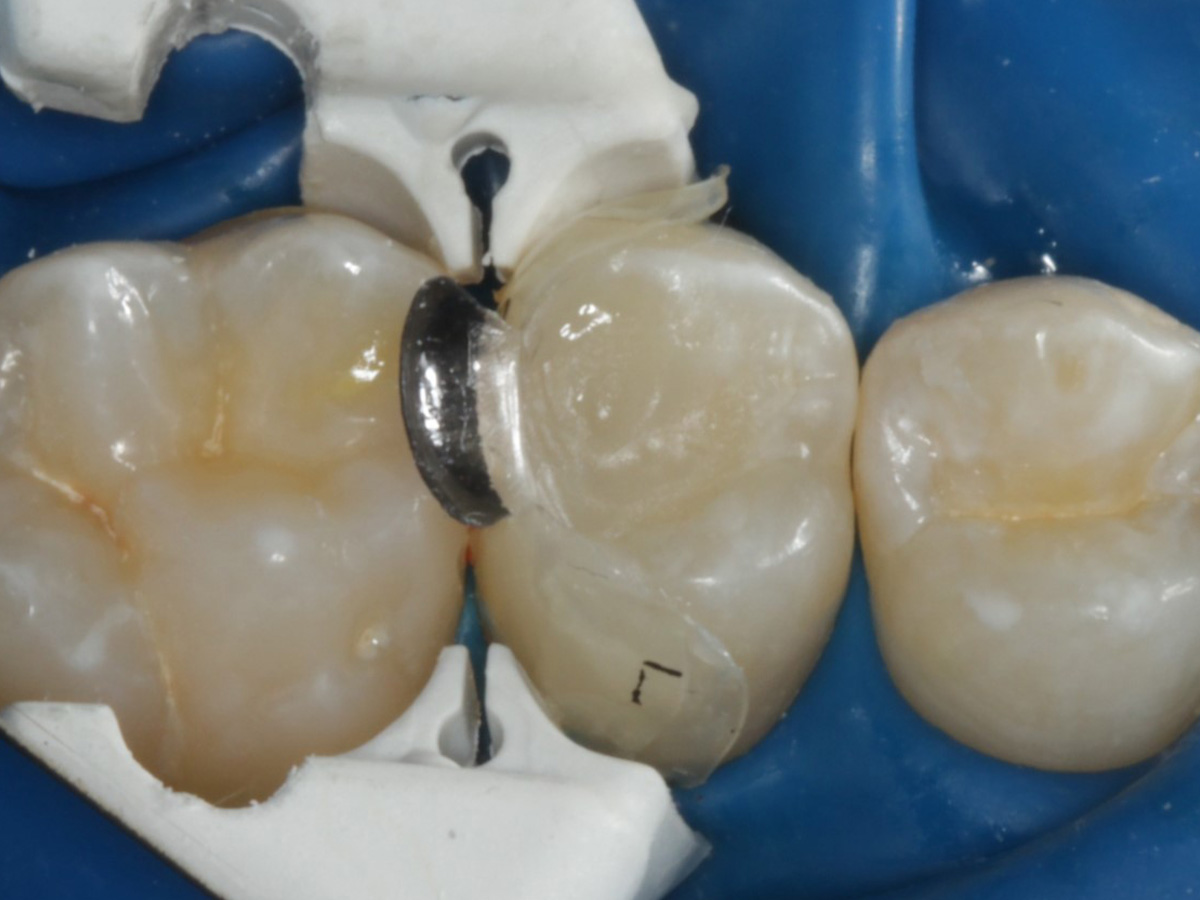

Abbildung 1

Bissflügelröntgenaufnahme, Approximalraumkaries an Zahn 25 distal

Abbildung 4

Schutz des Nachbarzahnes und des Kofferdams mit wiederverwandter Bioclear Biofit Matrize (gereinigt und sterilisiert)

Abbildung 9

Nach Applikation der Matrize: Evolve Schwarz Prämolar- 7 mm; Schmelzätzung

Abbildung 10

Nach Spray und Trocknung der Kavität: perfekte Adaptation der Matrize insbesondere tief subgingival